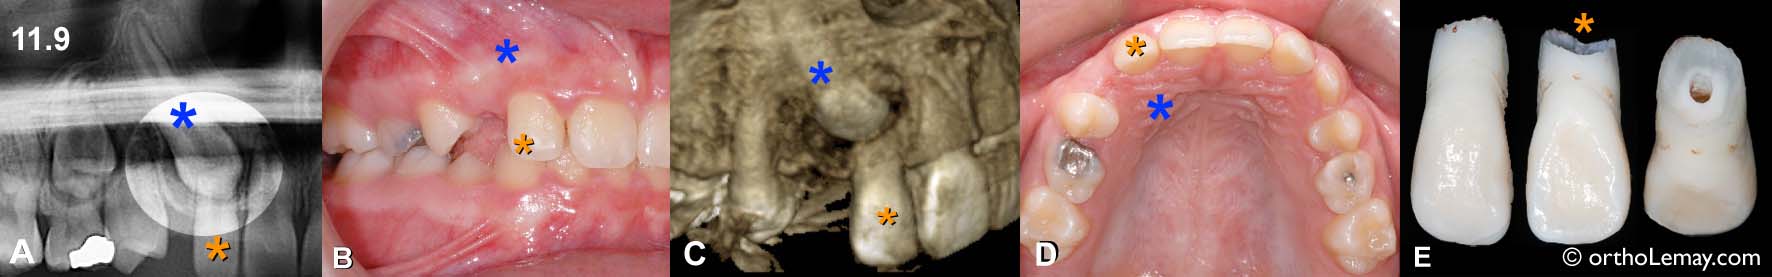

Cas BJ – Comparaison de la région de la canine supérieur droite incluse palatine (*bleu) sur une radiographie panoramique standard (A) prise de façon routinière mais seulement à l’âge de 11 ans (fille). (B) L’apparence clinique ne permet pas de deviner le grave problème de résorption radiculaire qui affecte la racine de l’incisive latérale (*orange) au point de l’avoir “usée” à ±70 %. Cliché extrait d’un scan 3D (TVFC) qui montre la destruction de la racine de la latérale par la canine. (D) Vue occlusale montrant la position approximative de la canine (*bleu). (E) Différentes vues de l’incisive latérale qui a dû être extraite car sa racine était trop usée par la canine ectopique.

➡ Pour en savoir plus sur ce cas et sur l’évaluation des canines incluses et ectopiques à l’aide de radiographies.